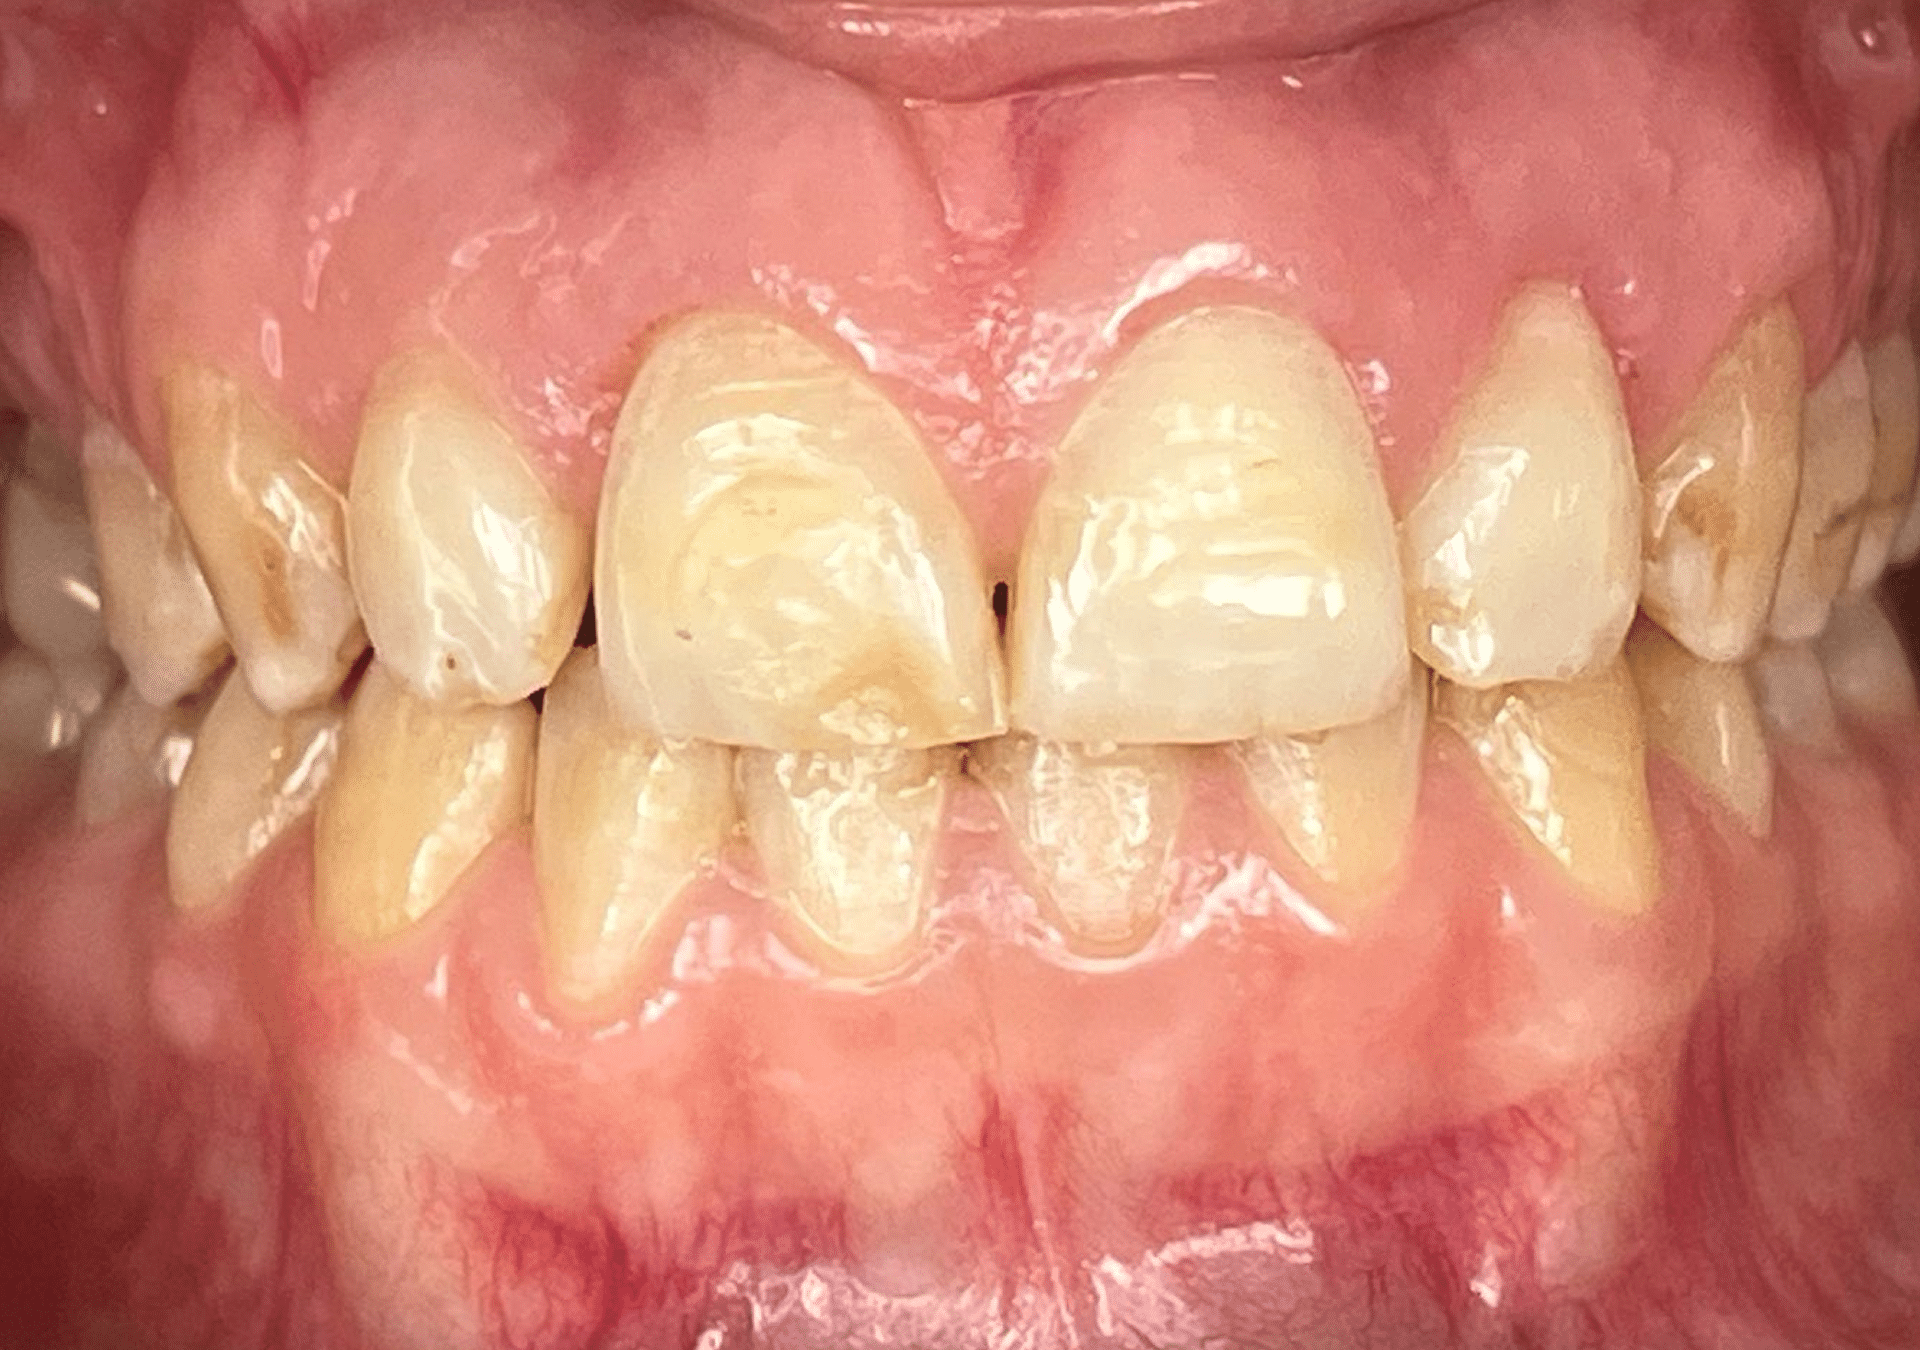

Caso 3

Rehabilitación con cerámica feldespática de dientes con tinción por tetraciclinas y malposición.